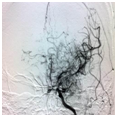

CTA及数字减影脑血管造影(DSA)

可检出脑动脉瘤,脑动静脉畸形,Moyamoya病等。